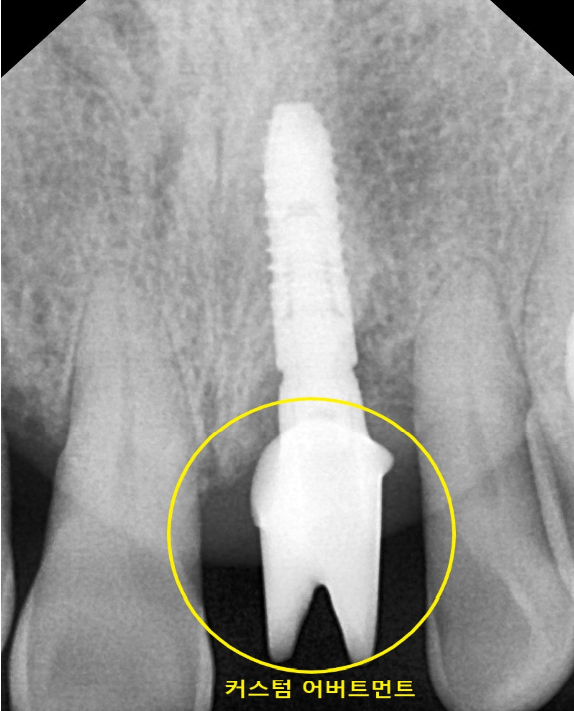

임플란트의 윗부분에 지대주 어버트먼트가 들어가게 되는데

기성 어버트먼트가 아닌

맞춤 커스텀 어버트먼트가 들어가게 됩니다.

커스텀 어버트먼트는 환자분의 임플란트 위에

치주의 생김새와 상부 보철을 고려한 어버트먼트입니다.

맞춤 정장을 생각하시면 쉬우실 겁니다.

기성 어버트먼트보다 비용이 많이 든다는 단점이 있으나

자연치아와 흡사한 임플란트 어버트먼트 구조로 되어 있어

장점이 더 많다고 생각합니다.

입안의 악궁과 치아의 각도 치주의 생김새가

모든 환자분이 다르기 때문에

기성보다는 커스텀어버트를

제작하여 진행해 드리고 있습니다.